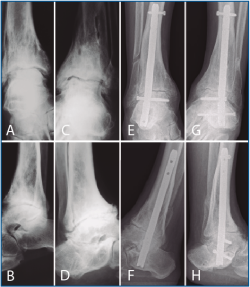

La segunda artrodesis se llevó a cabo durante el año siguiente a la primera intervención. La artrodesis fue tibioastragalina bilateral en 2 pacientes y tibiotalocalcánea (TTC) bilateral en el paciente restante. La estabilización ósea se realizó en un caso con 2 tornillos canulados Acutrak Plus® (Acumed, Hillsboro, EE. UU.) cruzados en ambos tobillos (Figura 1), en otro caso con clavo endomedular retrógrado T2 12 × 200 mm (Stryker, Schönkirchen, Alemania) en ambos tobillos (Figura 2) y en el último caso se utilizaron tornillos canulados Acutrak Plus® cruzados en el tobillo izquierdo y la técnica Putti en el tobillo derecho (Figura 3). La fijación de la artrodesis se realizó con el pie en plantígrado.

Figura 1. Caso 1. Varón de 47 años con artrosis primaria de tobillo bilateral. Corte coronal de tomografía axial computarizada (TAC) del tobillo derecho (A) e izquierdo (B) preoperatorio. Radiografía anteroposterior de artrodesis tibioastragalina con 2 tornillos canulados cruzados en tobillo derecho (C) e izquierdo (D) al año de la última intervención (tobillo derecho).